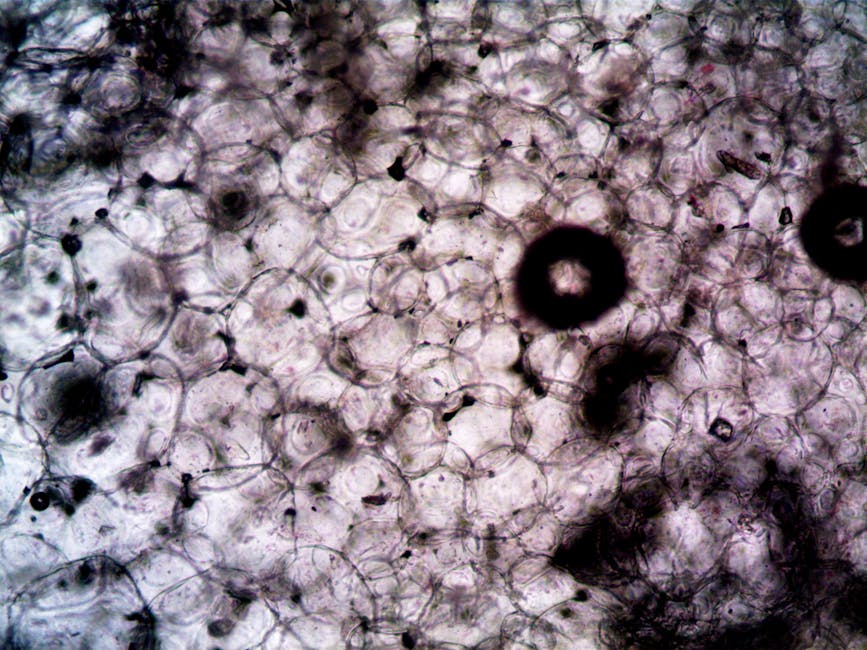

The study’s key findings are nothing short of remarkable. The researchers discovered that B cells, a type of immune cell, produce a protein that helps regulate muscle function during exercise. This protein, which is also involved in the production of antibodies, appears to play a critical role in maintaining muscle performance and preventing fatigue. The experiments, which involved both acute and chronic exercise models, demonstrated that mice with impaired B cell function exhibited reduced exercise endurance and increased muscle damage. These findings have significant implications for our understanding of the immune system’s role in exercise and highlight the need for further research into the complex relationships between immune cells, muscles, and physical activity.